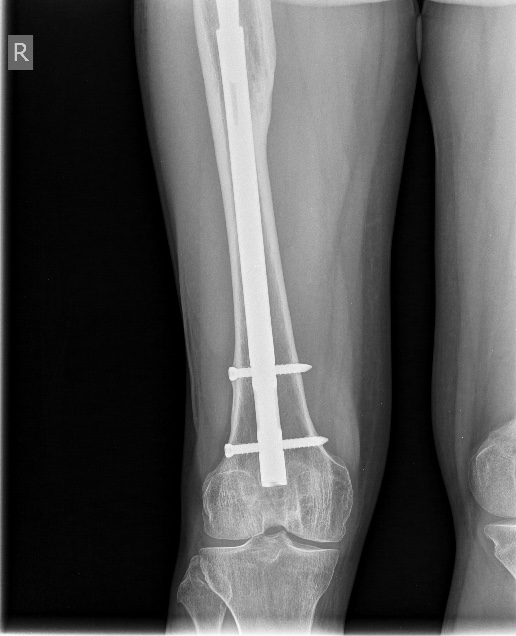

Закрытое штифтование с удлинением бесцементной ножки при переломах Vancouver B2/ B3 дает неожиданно для приверженцев традиционной догмы хорошие результаты.

Здесь первое наше наблюдение такого остеосинтеза с нестабильной ножкой. Прошло уже 6 лет - вот недавние снимки. Пациент не имеет жалоб, катается на коньках. Никакие дистальные винты не выдержали бы циклических нагрузок столько лет, если бы ножка оставалась нестабильной.